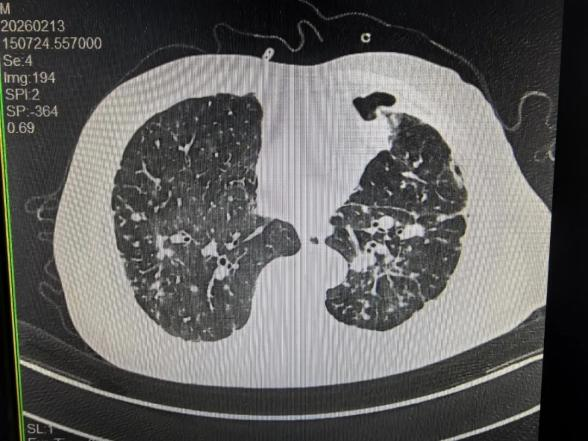

转机出现在春节前夕。持续漏气近一个月的胸管终于停止漏气,复查CT显示左肺几乎完全复张。春节过后,胸管引流量降至60ml,坚守一线的胸外科医生果断拔管。拔管后的老王逐步脱离吸氧,在病房自由活动,身体状况日益向好。